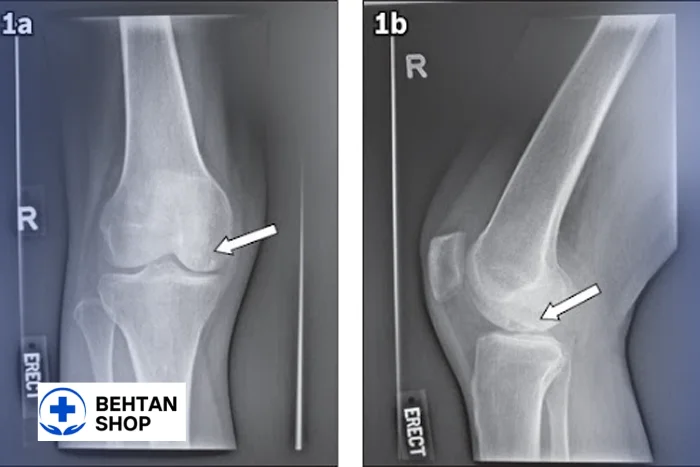

8. کیست استخوانی زانو (Bone Cyst)

کیست استخوانی در استخوانهای اطراف زانو مانند تیبیا، فمور یا پاتلا تشکیل میشود.

- ماهیت: فضاهای پر از مایع در داخل استخوان.

- علائم: اغلب بدون درد، اما در موارد رشد زیاد ممکن است ضعف استخوان یا شکستگی ایجاد کند.

- تشخیص: معمولاً بهطور اتفاقی در رادیولوژی یا MRI دیده میشود.

- اهمیت: باید از ضایعات توموری افتراق داده شود، زیرا برخی تومورهای خوشخیم یا نیمهبدخیم ظاهر مشابه دارند.

- درمان: بسته به اندازه و علائم از پیگیری دورهای تا جراحی.